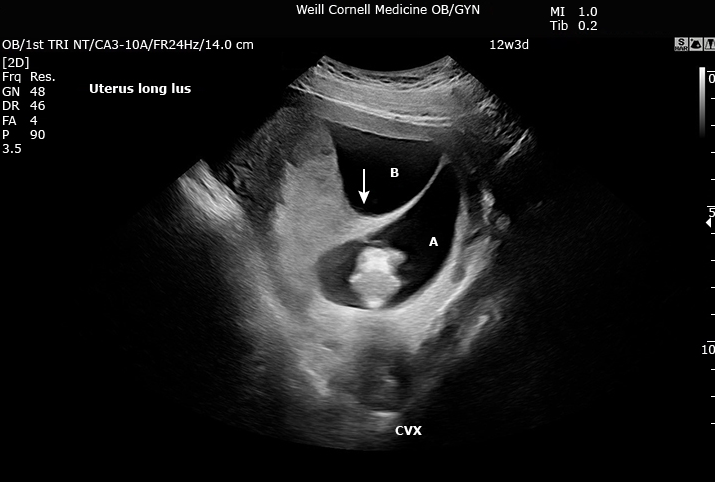

Signo de lambda que tipo de embarazo múltiple sugiere

Dichorionic diamniotic

Signo de la T que tipo de embarazo múltiple sugiere

Monochorionic diamniotic